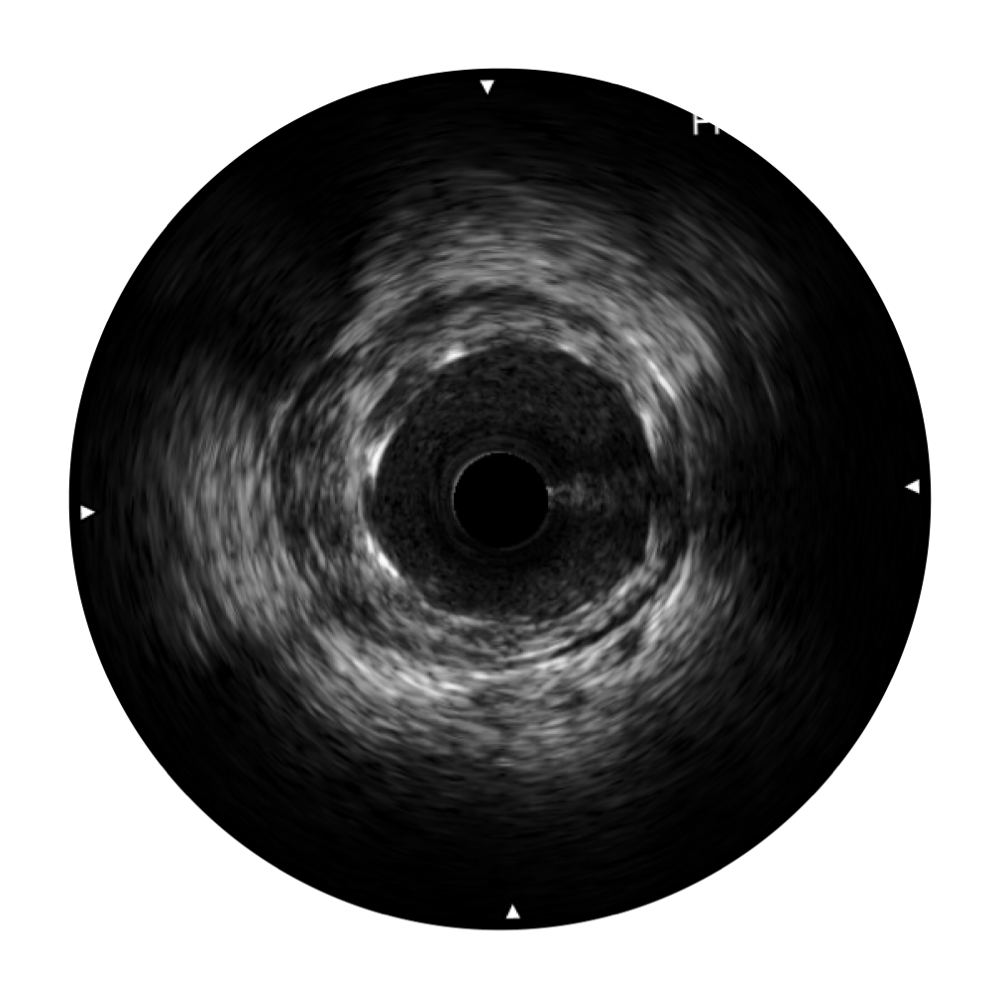

MILE米乐集团官网宽频IVUS图像

对比传统IVUS导管成像,MILE米乐集团官网宽频IVUS图像的近场支架梁显影更细腻,远场中膜外血管仍清晰可辨,兼顾远中近,兼顾分辨力与穿透深度